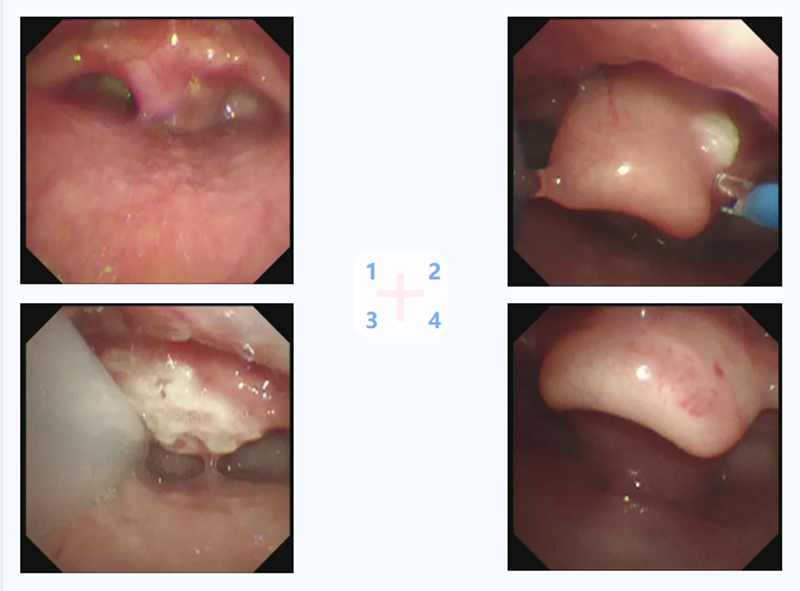

4个多月大的患儿婷婷,因“喉鸣2月余,咳嗽、喉间痰鸣3天”入住我院。入院后初步诊断:1.肺部感染;2.喉鸣原因待查,予抗感染、雾化及减轻气道炎症等对症治疗。入院第3天为患儿行支气管镜检查,诊断结果显示:喉软化0lney III型(重度)。

儿科专家团队经充分的术前评估和讨论后,决定为患儿行支气管镜下钬激光治疗重度喉软化。在患儿全身麻醉的情况下,通过支气管镜将钬激光光纤精准引导至患儿喉部病变部位,利用激光的高能量对会厌进行多点消融治疗。整个手术过程创伤小、出血少,术后予胃管喂养及抗反流,雾化吸入减轻水肿等对症治疗,术后1周患儿喉鸣逐渐减轻至消失,复查显示患儿恢复较好。出院半月后随访,患儿居家期间无咳嗽、喉鸣,可吸乳,体重较入院时增加1kg。

目前认为Olney的分型方法简单明了,且对手术具有明确的指导意义,分为以下四型:

Olney Ⅰ型:杓状软骨、楔状软骨及其黏膜向声门区脱垂;

Olney Ⅱ型:杓会厌襞缩短,会厌卷曲呈管状或Ω型会厌;

Olney Ⅲ型:会厌塌陷后移,吸气期遮盖声门;

Olney Ⅳ联合型:上述3型中有任何2型同时存在或3型俱存者。